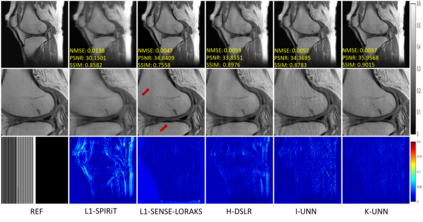

Recently, untrained neural networks (UNNs) have shown satisfactory performances for MR image reconstruction on random sampling trajectories without using additional full-sampled training data. However, the existing UNN-based approach does not fully use the MR image physical priors, resulting in poor performance in some common scenarios (e.g., partial Fourier, regular sampling, etc.) and the lack of theoretical guarantees for reconstruction accuracy. To bridge this gap, we propose a safeguarded k-space interpolation method for MRI using a specially designed UNN with a tripled architecture driven by three physical priors of the MR images (or k-space data), including sparsity, coil sensitivity smoothness, and phase smoothness. We also prove that the proposed method guarantees tight bounds for interpolated k-space data accuracy. Finally, ablation experiments show that the proposed method can more accurately characterize the physical priors of MR images than existing traditional methods. Additionally, under a series of commonly used sampling trajectories, experiments also show that the proposed method consistently outperforms traditional parallel imaging methods and existing UNNs, and even outperforms the state-of-the-art supervised-trained k-space deep learning methods in some cases.